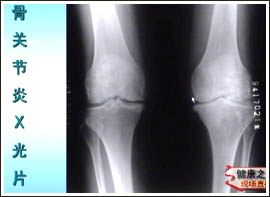

主持人:杭州郭女士 50岁 我这两年老是觉得腿疼,请问会是骨关节炎吗?如何确定呢? 翁习生:这个问题要根据具体情况进行分析,通常诊断骨关节炎要根据疼痛的特点、临床表现、以及医生检查后的信息做出一个诊断,必要的时候可以做一个X光片或化验检查等。 诊断要点 1、 近一个月内经常反复膝关节痛 2、 活动时有摩擦音 3、 膝关节晨僵≤30分钟 4、 年龄≥40岁 5、 膝关节骨端肥大

主持人:更严重的情况是不是就只能做人工关节置换术了? 邱贵兴:在年龄偏大、关节持续疼痛并活动受限、X光关节明显破坏的情况下,就应该考虑关节置换了。关节置换其实是一项很成熟的技术,早在20世纪30年代就已经出现了,最多的就是髋关节和膝关节的置换,美国每年进行髋关节和膝关节置换的患者各30万例,而在我国一亿三千万老人中进行膝关节置换的人数还不到一万。原因是我国的普及教育不够。来看一张图,关节置换实际上就是把关节表面的一层不平的部分去掉,换上一个很光滑的人工关节,这样症状可以明显改善。